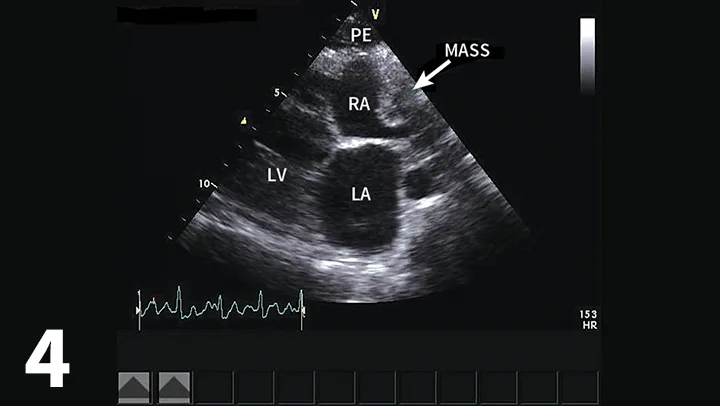

• Echocardiography confirms an echo-free space between the heart and the pericardium (Figure 1), may show cardiac tamponade (Figure 2), and may detect mass lesions.

Short-axis (hammerhead) view showing the left ventricle (LV), interventricular septum (IVS), and right ventricle (RV) surrounded by pericardial effusion (PE), which can be seen within the bright pericardium (asterisk). A short-axis view of the heart allows visualization of pericardial effusion by identifying an anechoic ring of fluid within the bright pericardium, helping differentiate the fluid from pleural effusion. Image courtesy of Meriel LeSueur, DVM

• Echocardiography